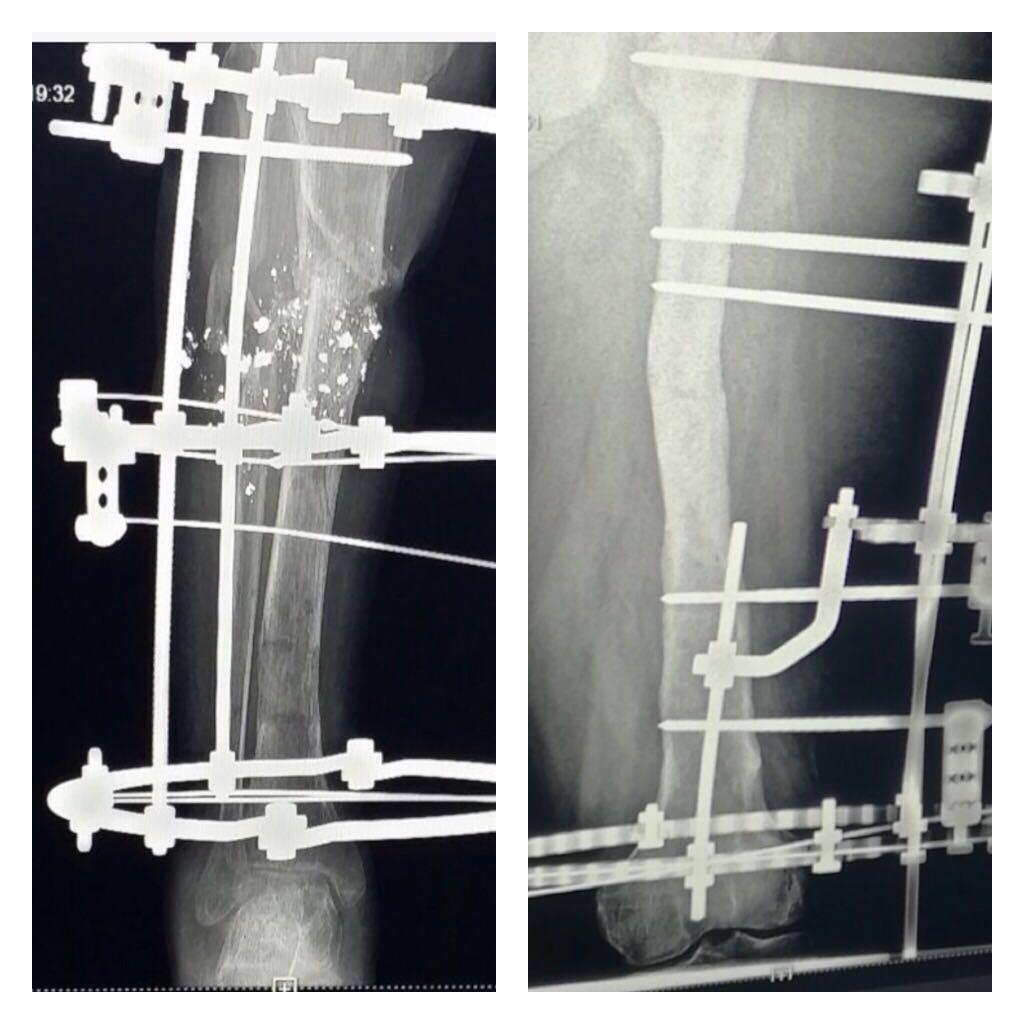

عمليتان نوعيتان لتعويض العظام المفقودة لشابين في جازان

قالت الصحة في جازان أن فريق جراحة العظام بمستشفى الملك فهد المركزي أجرى بنجاح عمليتين نوعيتين لشابين سعوديين حيث تم تعويض عظام مفقوده لهما، أحدهما من الفخذ الأيسر نتيجه حادث مروري قديم مع وجود التهاب نكروزي مزمن تم علاجه بجهاز اليزاروف، والعملية الثانية أجريت لشاب تعرض لإصابه بطلق ناري مع فقد بالعظم والتهاب مزمن تم استئصال العظم الملتهب وتم تعويض ٨ سم عن طريق نقل عظم من نفس عظمه الساق وبفضل الله تم تعويض طول الساق والتئام العظم، وقد تمت العمليتان بنجاح ولله الحمد. ------------------ جمعه الخياط